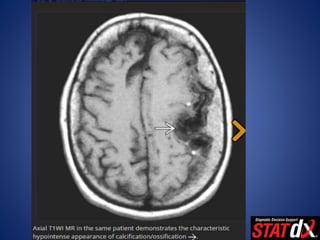

CT Findings

• NECT

– Sharply circumscribed smooth mass abutting dura

• Hyperdense (70-75%), isodense (25%)

– Hypodense (1-5%), fat density (rare lipoblastic subtype)

• Calcified (20-25%)

– Can be diffuse, focal, sand-like ("psammomatous")

– "Sunburst," globular, rim patterns

– Calcification correlates with slow growth in asymptomatic meningiomas

CT Findings • NECT –Sharply circumscribed smooth mass abutting dura • Hyperdense (70-75%), isodense (25%) – Hypodense (1-5%), fat density (rare lipoblastic subtype) • Calcified (20-25%) – Can be diffuse, focal, sand-like ("psammomatous") – "Sunburst," globular, rim patterns – Calcification correlates with slow growth in asymptomatic meningiomas • Necrosis, cysts, hemorrhage (8-23%) – Trapped CSF pools, cysts in adjacent brain common – Peritumoral hypodense vasogenic edema (60%) – Bone CT • Hyperostosis, irregular cortex, ↑ vascular markings